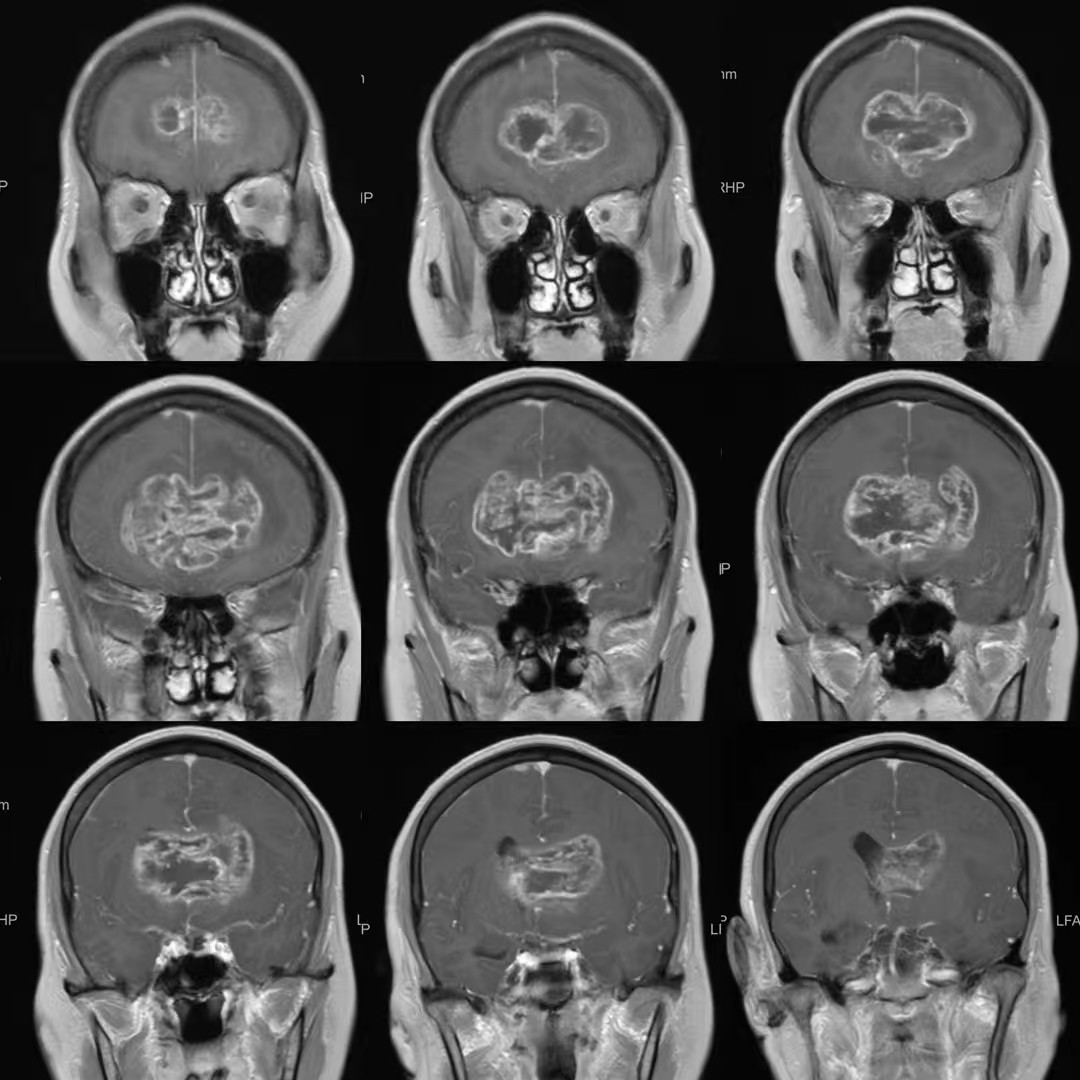

患者,女性,58岁,因“反应迟钝、记忆力下降1月,加重伴头痛、恶心、呕吐1周”入院。